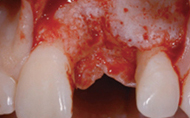

¡â Flap °Å»ó ÈÄ, °ñ °á¼ÕÀÌ °üÂûµÊ

¡â ÀÓÇöõÆ® ½Ä¸³ ÈÄ, Geistich Bio-Oss·Î °á¼ÕºÎ ÃæÀü

¡â À̽ĺÎÀ§¸¦ Geistich Bio-Gide·Î Çǰ³ ÇÔ

¡â ¿ÏÀüÇÑ ¿¬Á¶Á÷ Ä¡À¯¿Í ÃÖ»óÀÇ ½É¹ÌÀû °á°ú¸¦ º¼ ¼ö ÀÖÀ½